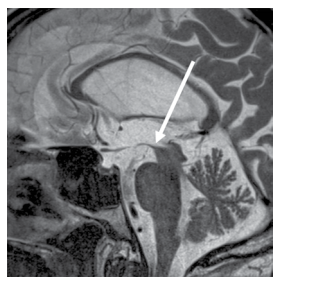

A imagem mostrada a seguir é observada em qual das seguintes doenças?